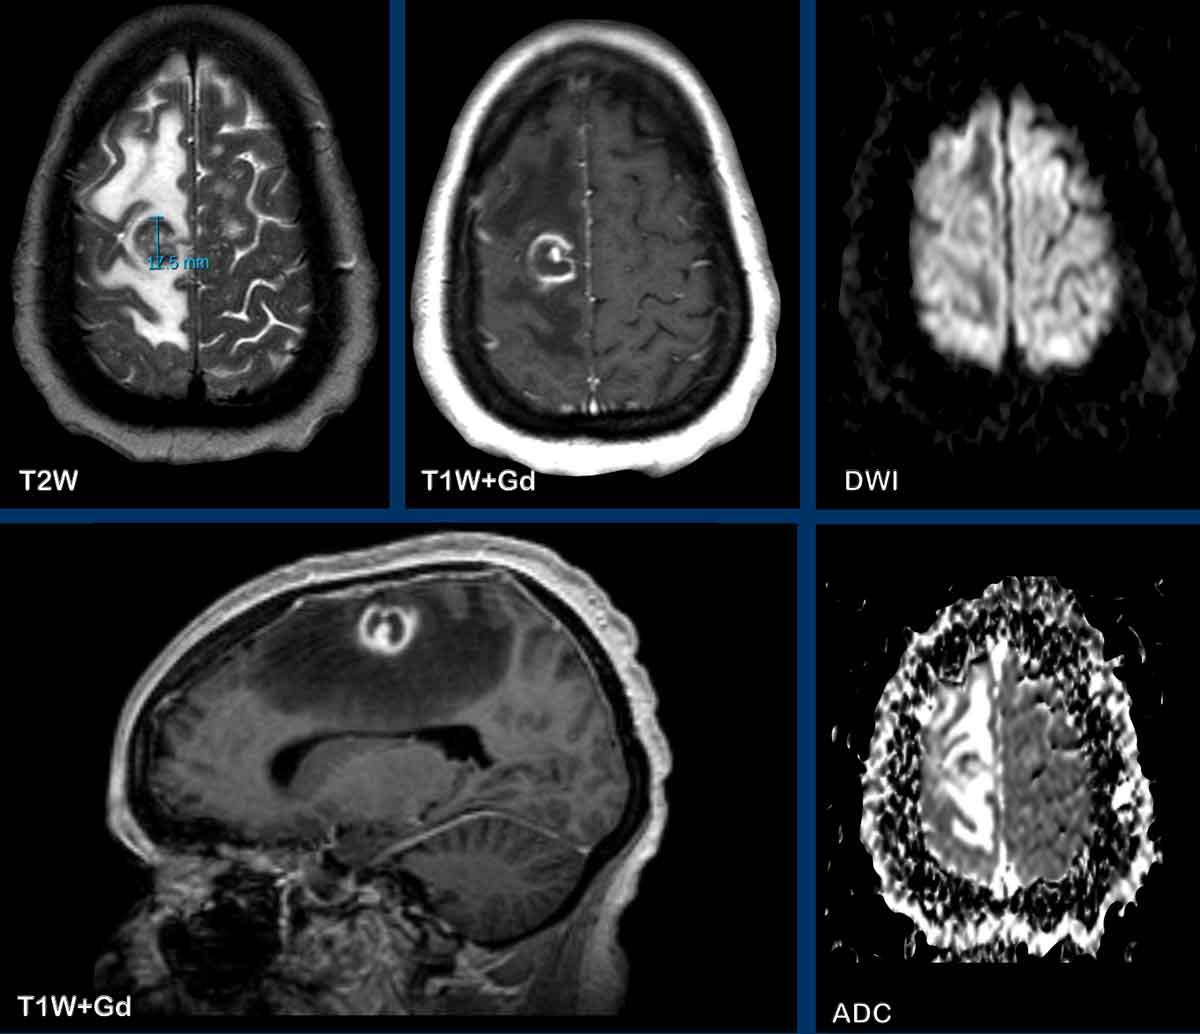

Đây là hình ảnh của bệnh nhân nam 55 tuổi với triệu chứng đau đầu.

Hãy quan sát hình ảnh trước rồi tiếp tục đọc.

Câu hỏi:

- Chẩn đoán có khả năng nhất là gì?

- Những dấu hiệu nào là điển hình cho chẩn đoán này?

Các dấu hiệu bao gồm:

- Có hai tổn thương ngấm thuốc dạng vòng được bao quanh bởi phù não

- Trên chuỗi xung T2W, dấu hiệu viền đôi (double rim sign) hiện diện ở tổn thương thùy trán trái.

- Có hạn chế khuếch tán ở trung tâm.

- Có ngấm thuốc viền nhẵn.

Tất cả các dấu hiệu này phù hợp với chẩn đoán áp-xe não.

Dấu hiệu viền đôi trên chuỗi xung T2W có thể gặp trong tới 75% các trường hợp.

Điển hình là có ngấm thuốc viền hoàn toàn và hạn chế khuếch tán, nhưng đôi khi ngấm thuốc không hoàn toàn do ổ áp-xe hướng về phía não thất, chuẩn bị đổ mủ vào hệ thống não thất.

Có thể thấy sự khởi đầu của quá trình này ở ổ áp-xe thùy trán phải.

Khi ổ áp-xe này vỡ vào não thất, viền ngấm thuốc sẽ bị gián đoạn và sẽ xuất hiện hạn chế khuếch tán trong lòng não thất.

Đây là hình ảnh của bệnh nhân nhập viện với triệu chứng đau đầu.

Hình ảnh

Có một tổn thương vùng đỉnh phải, với ngấm thuốc dạng viền và hạn chế khuếch tán ở trung tâm.

Chuỗi xung SWI cho thấy hiệu ứng từ cảm (susceptibility) ở viền, được cho là do các gốc tự do thuận từ được tạo ra bởi đại thực bào.

Ngoài ra còn có một điểm chảy máu ở mặt bụng, nơi khuếch tán không bị hạn chế.

Sự ngấm thuốc mờ nhạt bên ngoài viền trong, do rò rỉ hàng rào máu-não, có thể gây khó khăn trong việc phân biệt với khối u, tuy nhiên hạn chế khuếch tán kết hợp với thể tích máu não tương đối (rCBV) thấp (không hiển thị) giúp xác định chẩn đoán áp-xe là có khả năng nhất